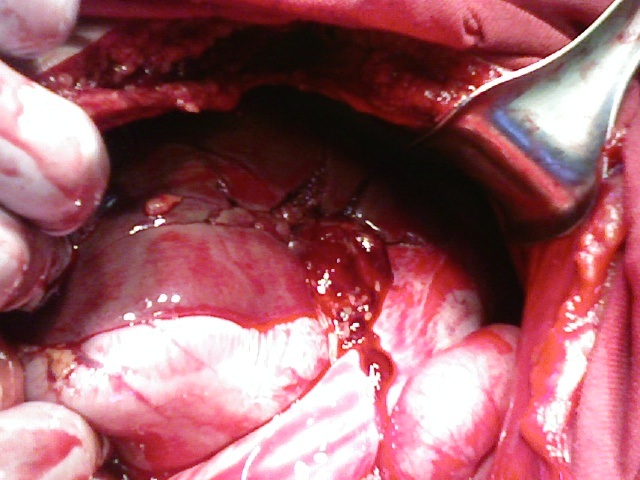

Оперативное вмешательство при тупой травме печени

S36.1 Травма печени или желчного пузыря